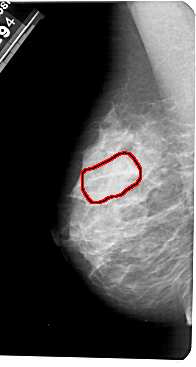

A_1183_1.LEFT_MLO

LEFT_MLO LINES 5491 PIXELS_PER_LINE 2926 BITS_PER_PIXEL 12 RESOLUTION 43.5 OVERLAY

FILE: A_1183_1.LEFT_MLO.OVERLAY

TOTAL_ABNORMALITIES 1

ABNORMALITY 1

LESION_TYPE CALCIFICATION TYPE PUNCTATE DISTRIBUTION REGIONAL

ASSESSMENT 4

SUBTLETY 1

PATHOLOGY MALIGNANT

TOTAL_OUTLINES 1

BOUNDARY